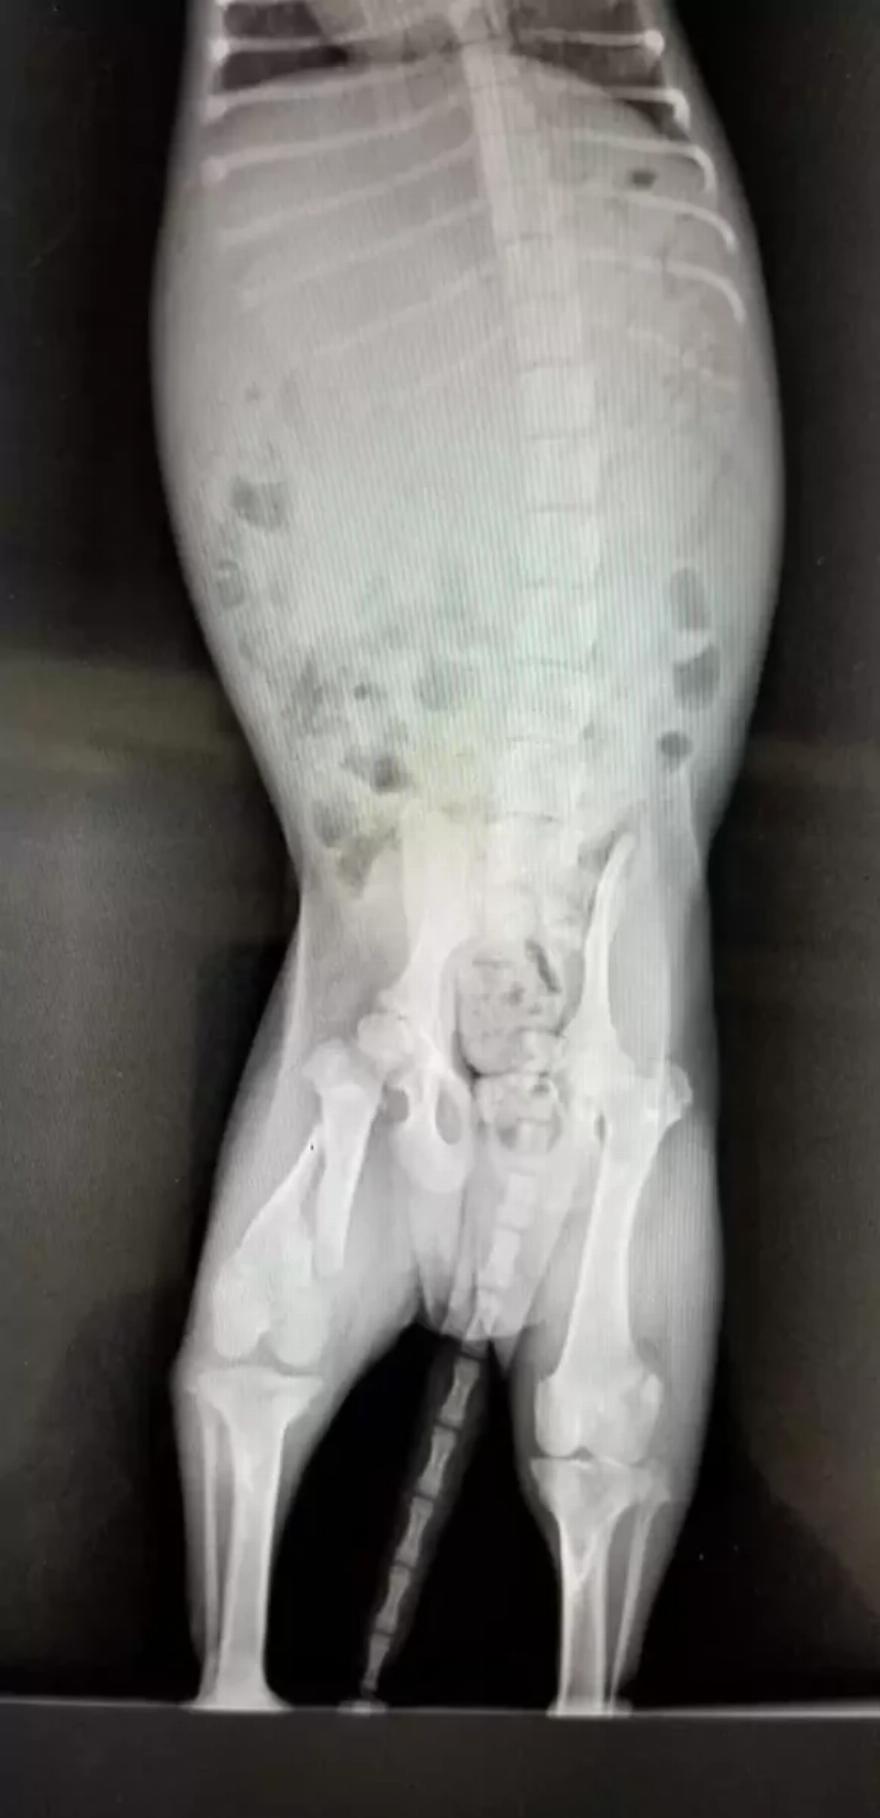

Το προσωπικό ανακάλυψε αργότερα ότι το κουτάβι είχε επίσης ένα σπασμένο πόδι, το οποίο θα χρειαζόταν χειρουργική επέμβαση. Πιστεύουν ότι κάποιος το πέταξε από τη γέφυρα και δεν πέτυχε το νερό, με αποτέλεσμα το κουτάβι να προσγειωθεί στο έδαφος.